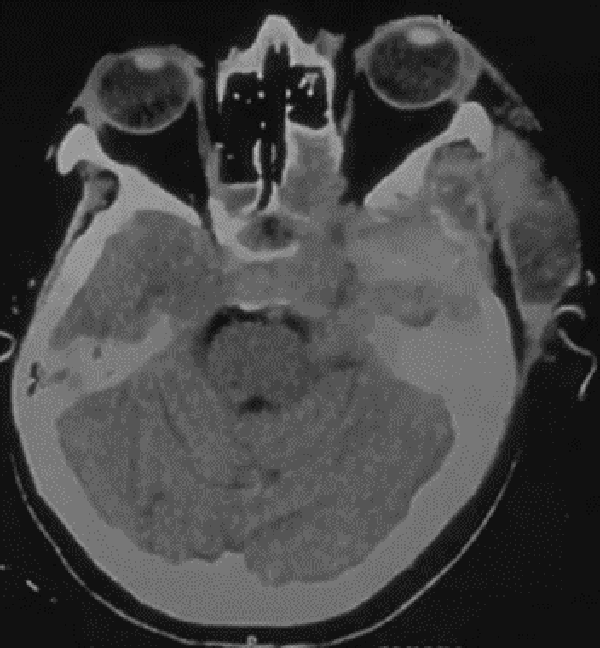

Treinta días luego de la cirugía nos volvió a consultar por presentar un síndrome febril y una colección en el sitio quirúrgico. Al examen físico, respecto al post-operatorio al momento del alta, se evidenció un aumento notable de la proptosis. Se realizó una tomografía computada (TC) que evidenció una colección epidural con realce luego de la inyección de contraste endovenoso y una lesión en seno cavernoso izquierdo de mayor tamaño al encontrado en la TC post-operatoria previa (Fig 2-Fig 3). Ante el aumento de volumen de la lesión previa se sospechó que el remanente tumoral se había abscedado. Se decidió realizar una toilette del sitio quirúrgico y una resección de la lesión. El hecho llamativo fue que el crecimiento del remanente tumoral no fue a expensas de un proceso infeccioso sino a expensas de proliferación neoplásica. La anatomía patológica evidenció que se trataba de un tumor maligno de la vaina de nervio periférico (TMVNP). Durante su estadía en la unidad de terapia intensiva (UTI), y como protocolo de nuestra institución, se realizó un hisopado para el SARS-COV-2 el cual resultó positivo. Como resultado de ello, su cuadro clínico fue empeorando progresivamente, evolucionando hacia una insuficiencia respiratoria que requirió asistencia respiratoria mecánica. La paciente falleció diez días después de la última intervención quirúrgica.

Figura 3:Tomografía Computada de encéfalo simple axial postquirúrgica al día 30 de la cirugía. Se evidencia aumento del tamaño tumoral, una colección epidural y un aumento de la proptosis.